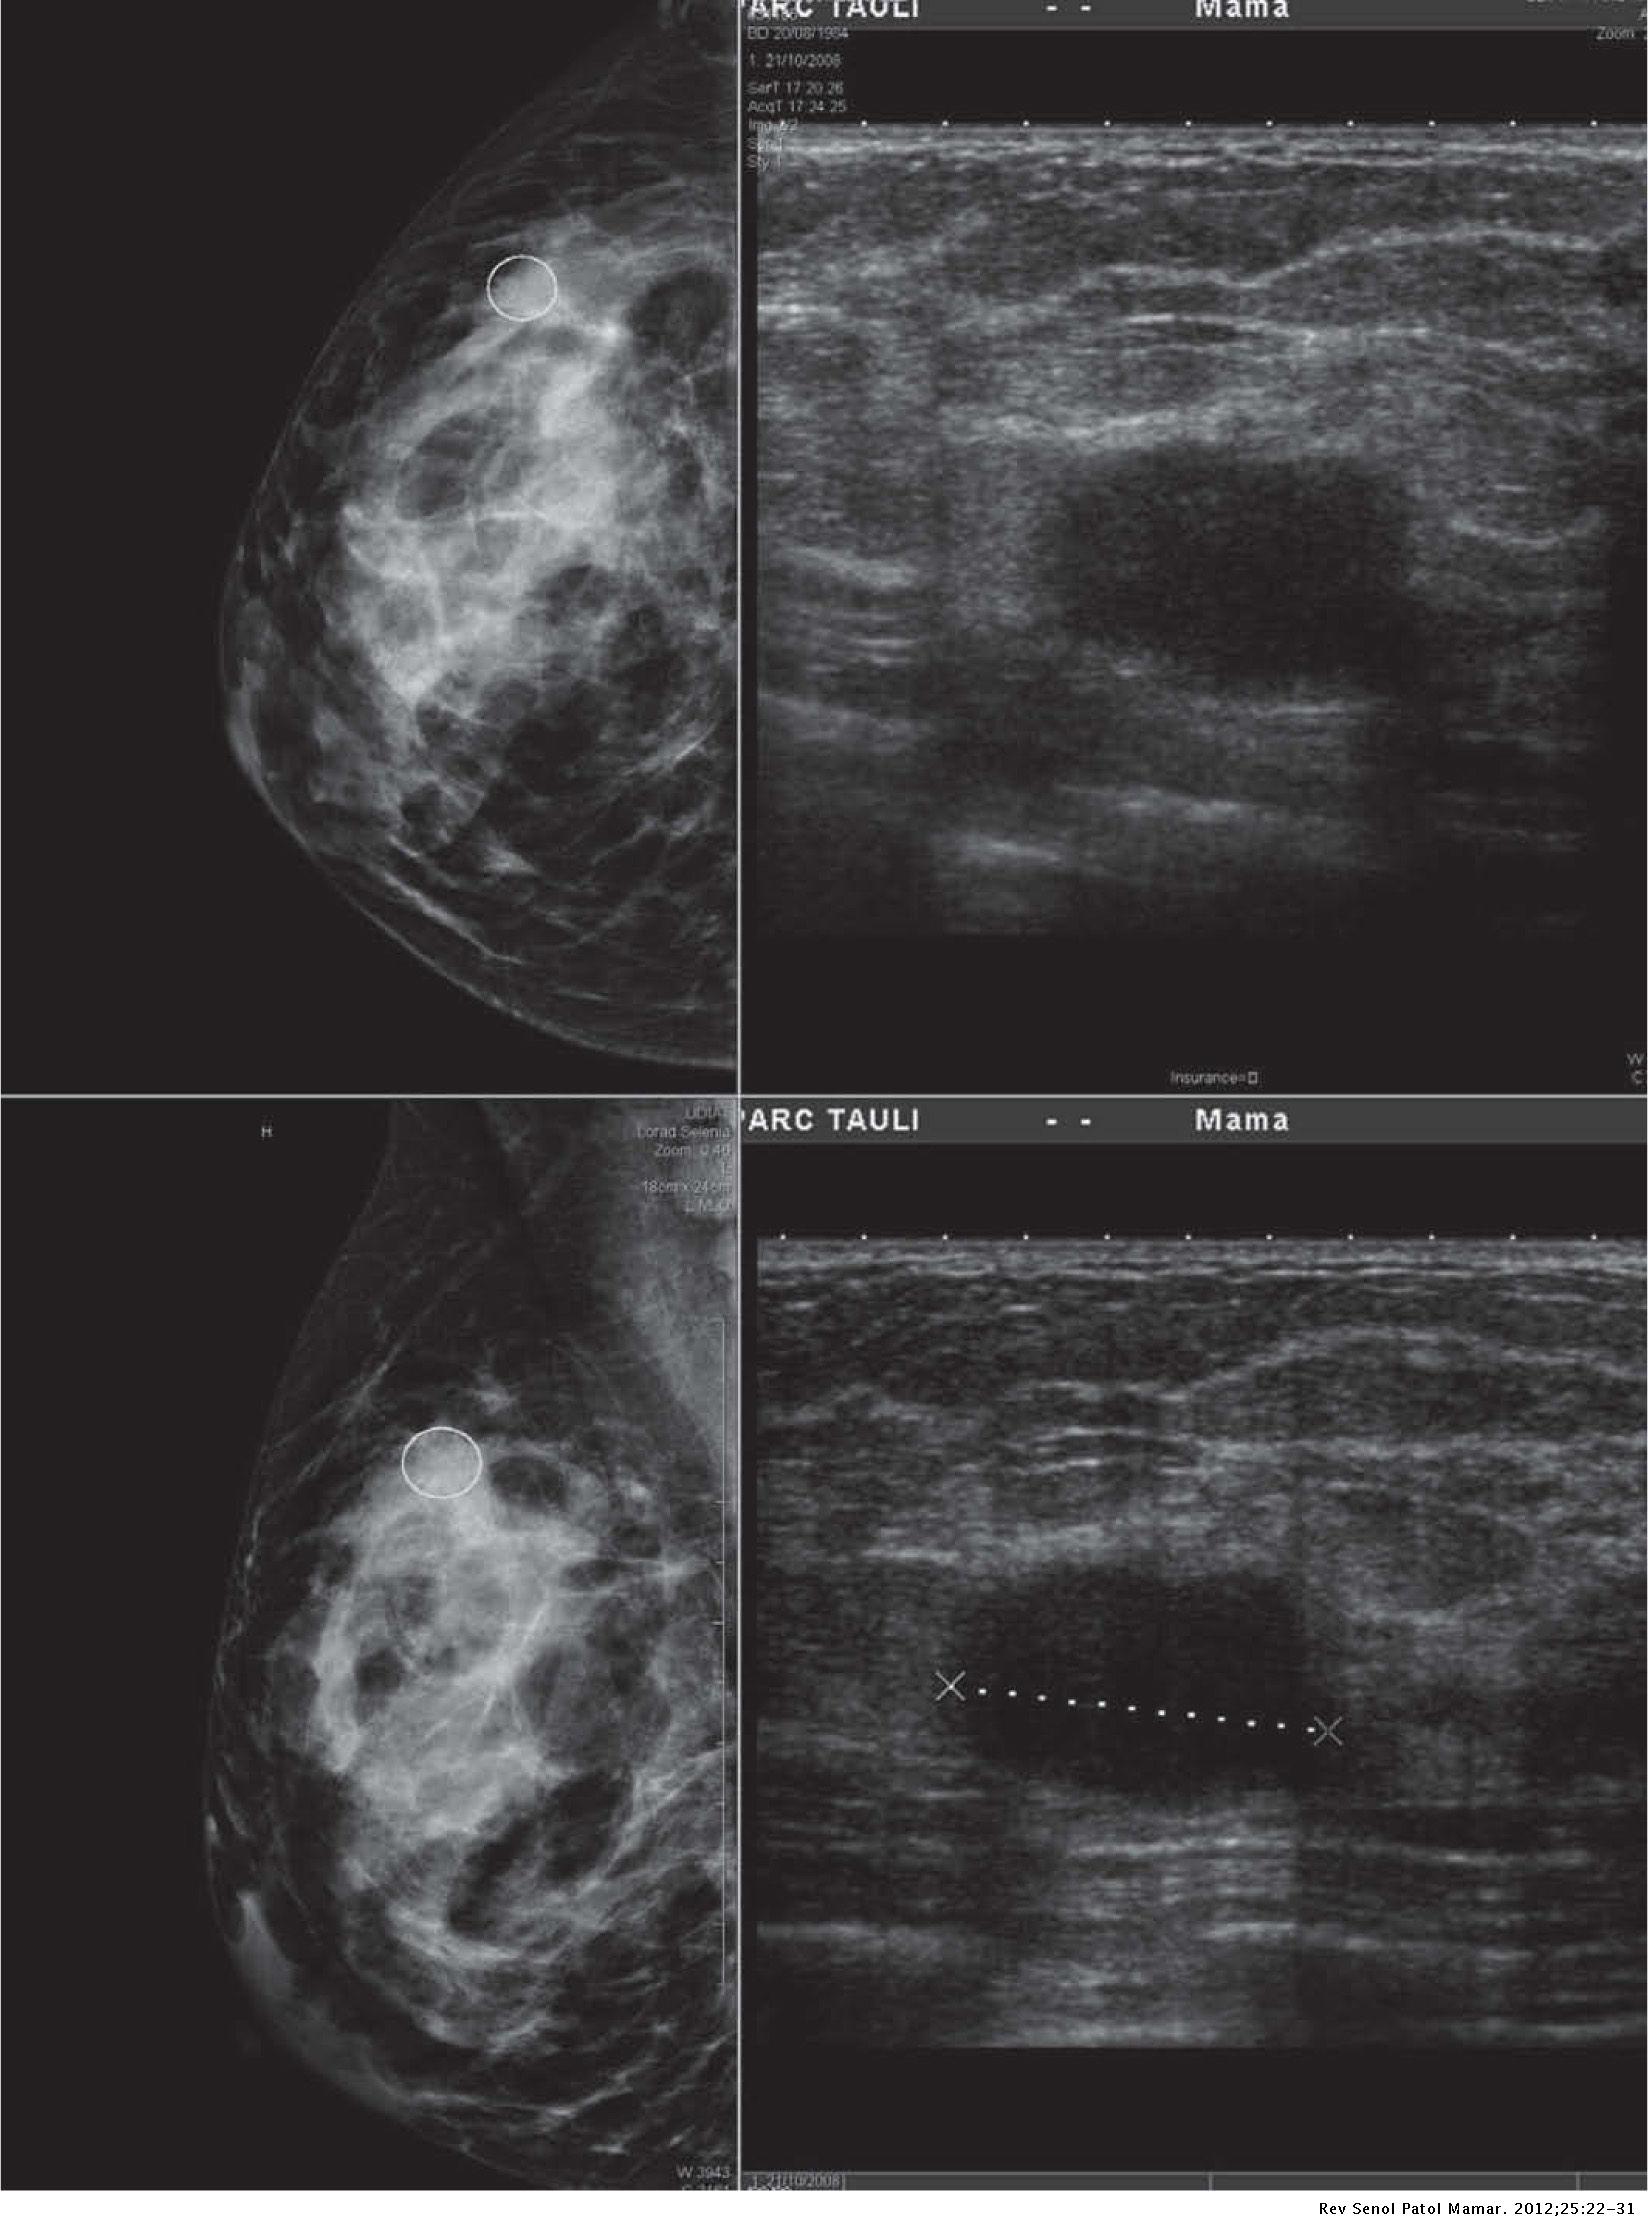

a,b Paziente di 55 anni con carcinoma duttale infiltrante (diametro... Download Scientific Diagram

Características de imagen del carcinoma triple negativo Revista de Senología y Patología